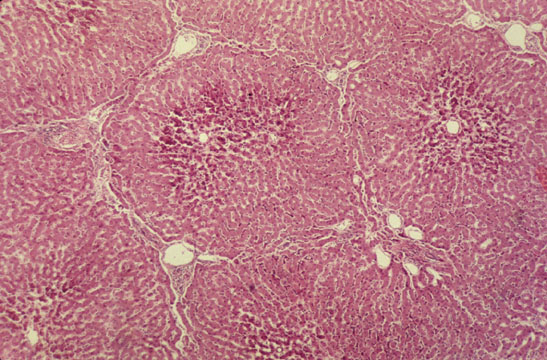

Lobule

Fig 2 - Under light microscopy,the lobule has a roughly polygonal shape.The central dark dot is the central vein and the peripharal darker areas are the 4-5 portal spaces at the angles of the polygon.